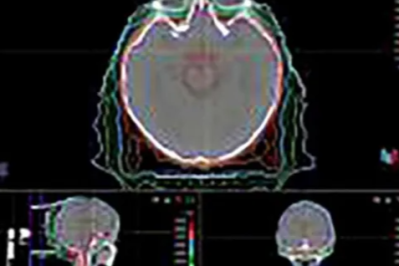

河北一洲肿瘤医院是经河北省卫健委批准设立,集医疗、教学、科研、预防和康复于一体的三级肿瘤专科医院。医院坐落于河北省涿州市码头镇301保障基地,紧邻北京,交通便利,环境优美,设施齐全。在医院各项工作中,我们时刻以患者为中心,秉承“质量第一、服务至上”的宗旨,竭诚为每一位患者提供高标准、高品质的医疗服务! 医院总投资近30亿元,有20多万平方米的门诊住院大楼,并配置床位1500张。现设有放射治疗中心和肿瘤综合科、肿瘤内科、肿瘤外科、妇科、中医科、ICU、麻醉科、检验科、药学部、放射诊断科、超声医学科、病理科等30多个临床和医技科室,其中放疗中心包括头颈肿瘤放疗科(放疗一科)、胸部肿瘤放疗科(放疗二科)、腹部肿瘤放疗科(放疗三科)、盆腔肿瘤放疗科(放疗五科)及儿童及神经系统肿瘤放疗科(放疗六科)。医院以质子治疗为龙头,以放疗为特色,同时兼顾手术、化疗、靶向、免疫、中医等综合肿瘤治疗。 医院广纳人才,聘请国内外知名三甲医院专家,包括解放军总医院、海军总医院、空军总医院、火箭军医院、北京大学第一医院等医院专家,此外还与来自美国MD安德森、宾夕法尼亚大学肿瘤质子治疗中心的专家共同组成强大的肿瘤多学科诊疗(MDT)团队,开展先进的肿瘤质子放射治疗,为广大肿瘤患者提供国际化、个体化的高品质医疗服务。 放射治疗中心设立在河北一洲肿瘤医院内,引进比利时IBA Proteus PLUS质子治疗系统,配备有先进的 CBCT图像引导系统、呼吸门控技术、笔形束扫描技术及360°旋转机架。质子加速器由5个治疗室组成,其中4个旋转机架治疗室、一个固定束治疗室;4个笔形束扫描治疗头,一个通用治疗头(具备双散射及笔形束扫描两种功能),是目前世界上技术先进、功能完备、规模较大的质子治疗中心之一。同时医院还配置2台TOMO HD、 1台Versa HD、1台VMAT直线加速器、1台ICON头部伽马刀、2台CT模拟定位机和1台MRI模拟定位机等精准放疗设备,并配有多台CT、MRI、PET/CT和ECT等先进影像诊疗设备,可为患者提供从检查、诊断到治疗的 “一站式"医疗服务。 一洲肿瘤医院与北京大学肿瘤医院、首都医科大学附属北京儿童医院、清华大学工程物理系等一系列单位开展全方位深度密切合作,致力于发展先进的肿瘤精准放疗技术,打造肿瘤质子治疗技术行业高地,造福更多海内外肿瘤患者特别是儿童肿瘤患者。